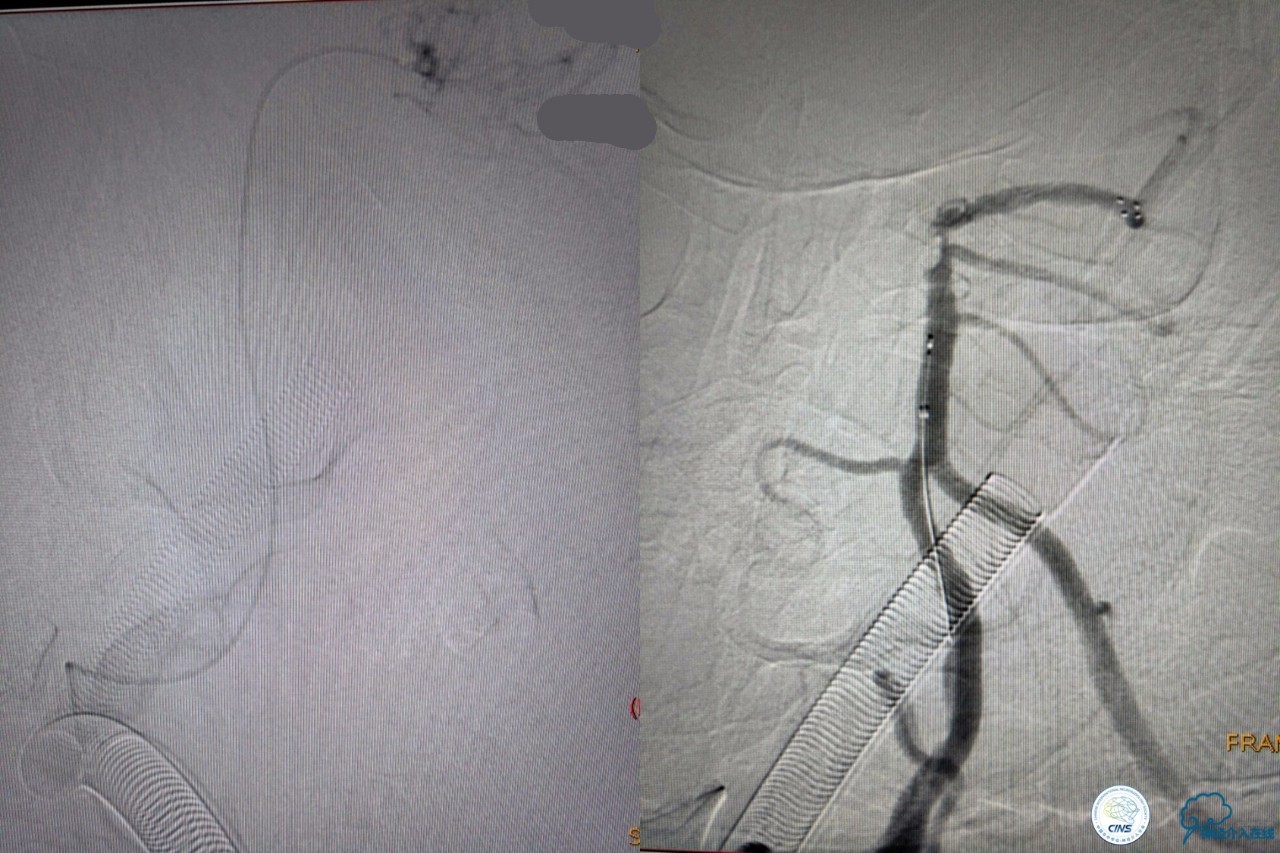

6F导引导管到位至RV2远端,rebar-18微导管及transand微导丝至右侧大脑后动脉P1远端。

solitaireAB4-20mm支架取栓。

基底动脉顶端仍有大量血栓,双侧大脑后动脉未见显影,双侧小脑上动脉再通。再次取栓?还是动脉溶栓?

决定导管内给予替罗非班6ml,复查造影BA顶端仍闭塞,第二次取栓。